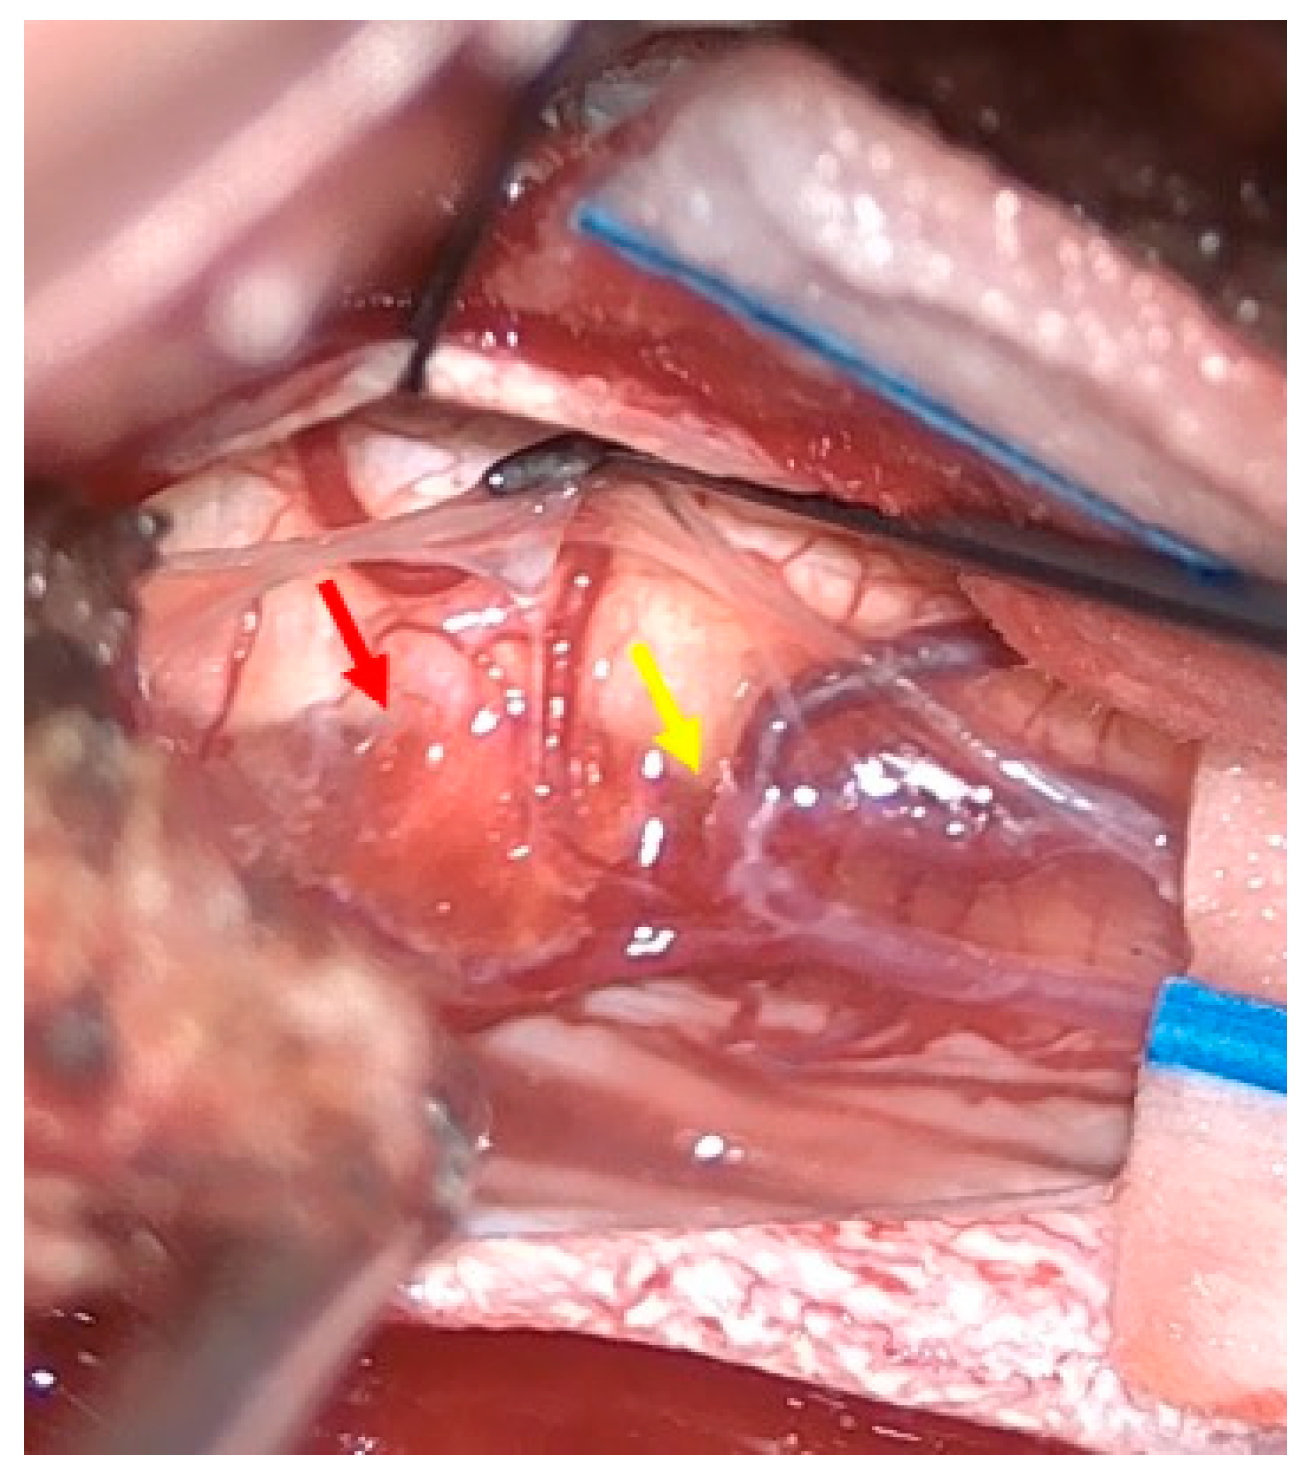

Figure 4.

Intraoperative findings. The hemangioma (red arrow) and arteriovenous fistula (yellow arrow).